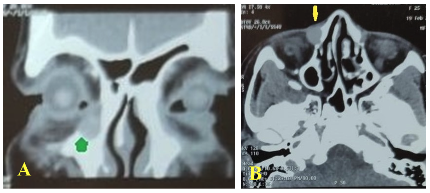

Examination of the eye was essentially normal, and best corrected visual acuity was 6/6 in both eyes. Lacrimal syringing revealed patent lacrimal pathway on both sides. Nasal examination ruled out any local pathology. Noncontrast computed tomography orbit axial scan showed nodular soft tissue in the middle part of the right nasolacrimal duct (Figure 2). An excision biopsy was planned. A cystic mass measuring 0.5 × 0.5 × 0.3 cm (Figure 3) was excised in toto; the lesion appeared to be separate from the nasolacrimal duct, and probing confirmed the same.